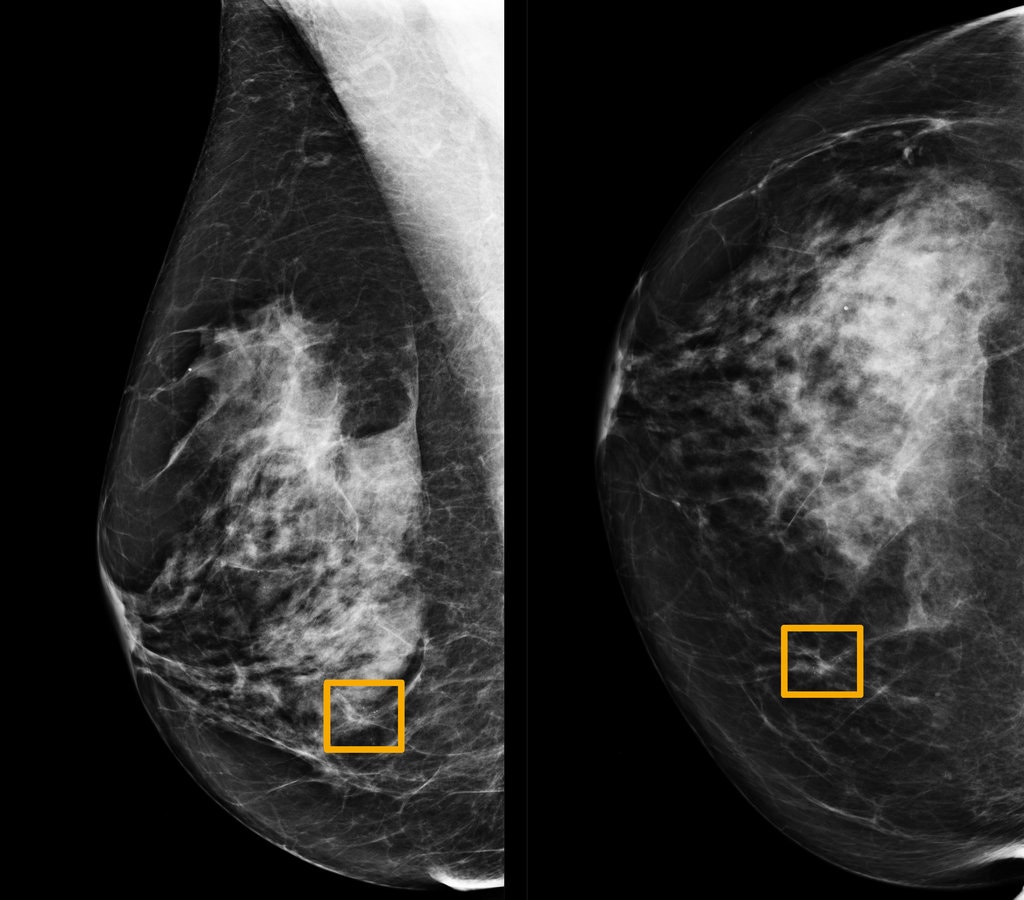

Immagine mammografica contenuta nel campione utilizzato dallo studio "International evaluation of an AI system for breast cancer screening", pubblicato da Google su Nature a gennaio del 2020. I rettangoli gialli indicano le aree in cui il sistema di intelligenza artificiale ha individuato formazioni tumorali che i sei radiologi esperti coinvolti nello studio non sono stati in grado di riconoscere.

Nel 2015 un gruppo di ricercatori statunitensi ha provato a misurare il grado di accordo all'interno di un gruppo di patologi nell'interpretazione delle immagini di tessuti prelevati durante biopsie mammarie. I tessuti appartenevano a 240 donne, affette da diverse forme di anomalia cellulare: da quelle benigne, a quelle atipiche, al carcinoma duttale in situ (considerato pre-canceroso) fino alle forme invasive (quelle in cui le cellule tumorali superano le pareti dei dotti e invadono il tessuto circostante). Un comitato di tre patologi esperti analizzò le immagini e stabilì una diagnosi consensuale considerata di riferimento. Le immagini vennero quindi mostrate a 115 patologi che si trovarono d'accordo con la diagnosi consensuale solo nel 75,3% dei casi. Il grado di accordo però non risultò uniforme per tutte le categorie tumorali. Per le forme invasive l'accordo raggiunse il 96%, al contrario per le forme atipiche solo il 48%. Come scrive Hannah Fry nel suo libro 'Hello World': "Una probabilità del genere equivale a lanciare una moneta per formulare la diagnosi. Testa e potresti praticare una mastectomia non necessaria. Croce e potresti perdere l'occasione di trattare il cancro nella sua fase iniziale. Insomma, l'impatto può essere devastante. Quando la posta in gioco è così alta, la precisione è ciò che conta di più. E se un algoritmo potesse fare meglio?"Anche nei programmi di screening mammografico, il passo diagnostico precedente alla biopsia, il tasso di errore non è trascurabile. La American Cancer Society stima che il test ha il 20% di falsi negativi, tumori che non vengono diagnosticati. Per quanto riguarda i falsi positivi, formazioni benigne scambiate per tumori, sempre la American Cancer Society stima che il 50% delle donne che si sottopongono annualmente a una mammografia avrà un falso positivo nell'arco di 10 anni di indagini. È stato quindi accolto con favore lo studio pubblicato da Google all'inizio di quest'anno sulla rivista Nature dal titolo "International evaluation for an AI system for breast cancer screening". L'articolo presenta le performance di un algoritmo per l'analisi delle immagini mammografiche. Per farlo i ricercatori hanno utilizzato un campione di immagini ottenute da 76 mila donne nel Regno Unito e 15 mila donne negli Stati Uniti per cui sono noti sia la diagnosi pronunciata dal radiologo che ha valutato per primo la mammografia sia il decorso di salute o malattia. Dopo aver allenato l'algoritmo su un sottoinsieme delle immagini, lo hanno testato sull'insieme restante, confrontando i risultati con la prima diagnosi del radiologo e con la 'vera' diagnosi dedotta dai decorsi di salute o malattia. Da questo confronto è emerso che: per il campione statunitense l'intelligenza artificiale riduce del 9,4% la percentuale di falsi negativi e del 5,4% quella di falsi positivi, mentre per il campione britannico la riduzione è del 2,7% e dell'1,2% rispettivamente. I ricercatori hanno poi effettuato una sfida tra l'algoritmo e sei radiologi esperti a cui sono state sottoposte 500 mammografie, insieme ad alcune informazioni che sono normalmente disponibili come l'età della paziente e altri screening precedenti. Anche in questo confronto il sistema si comporta meglio dei radiologi, anche se esistono dei casi di tumore diagnosticati solo dai radiologi e non dall'intelligenza artificiale e viceversa.